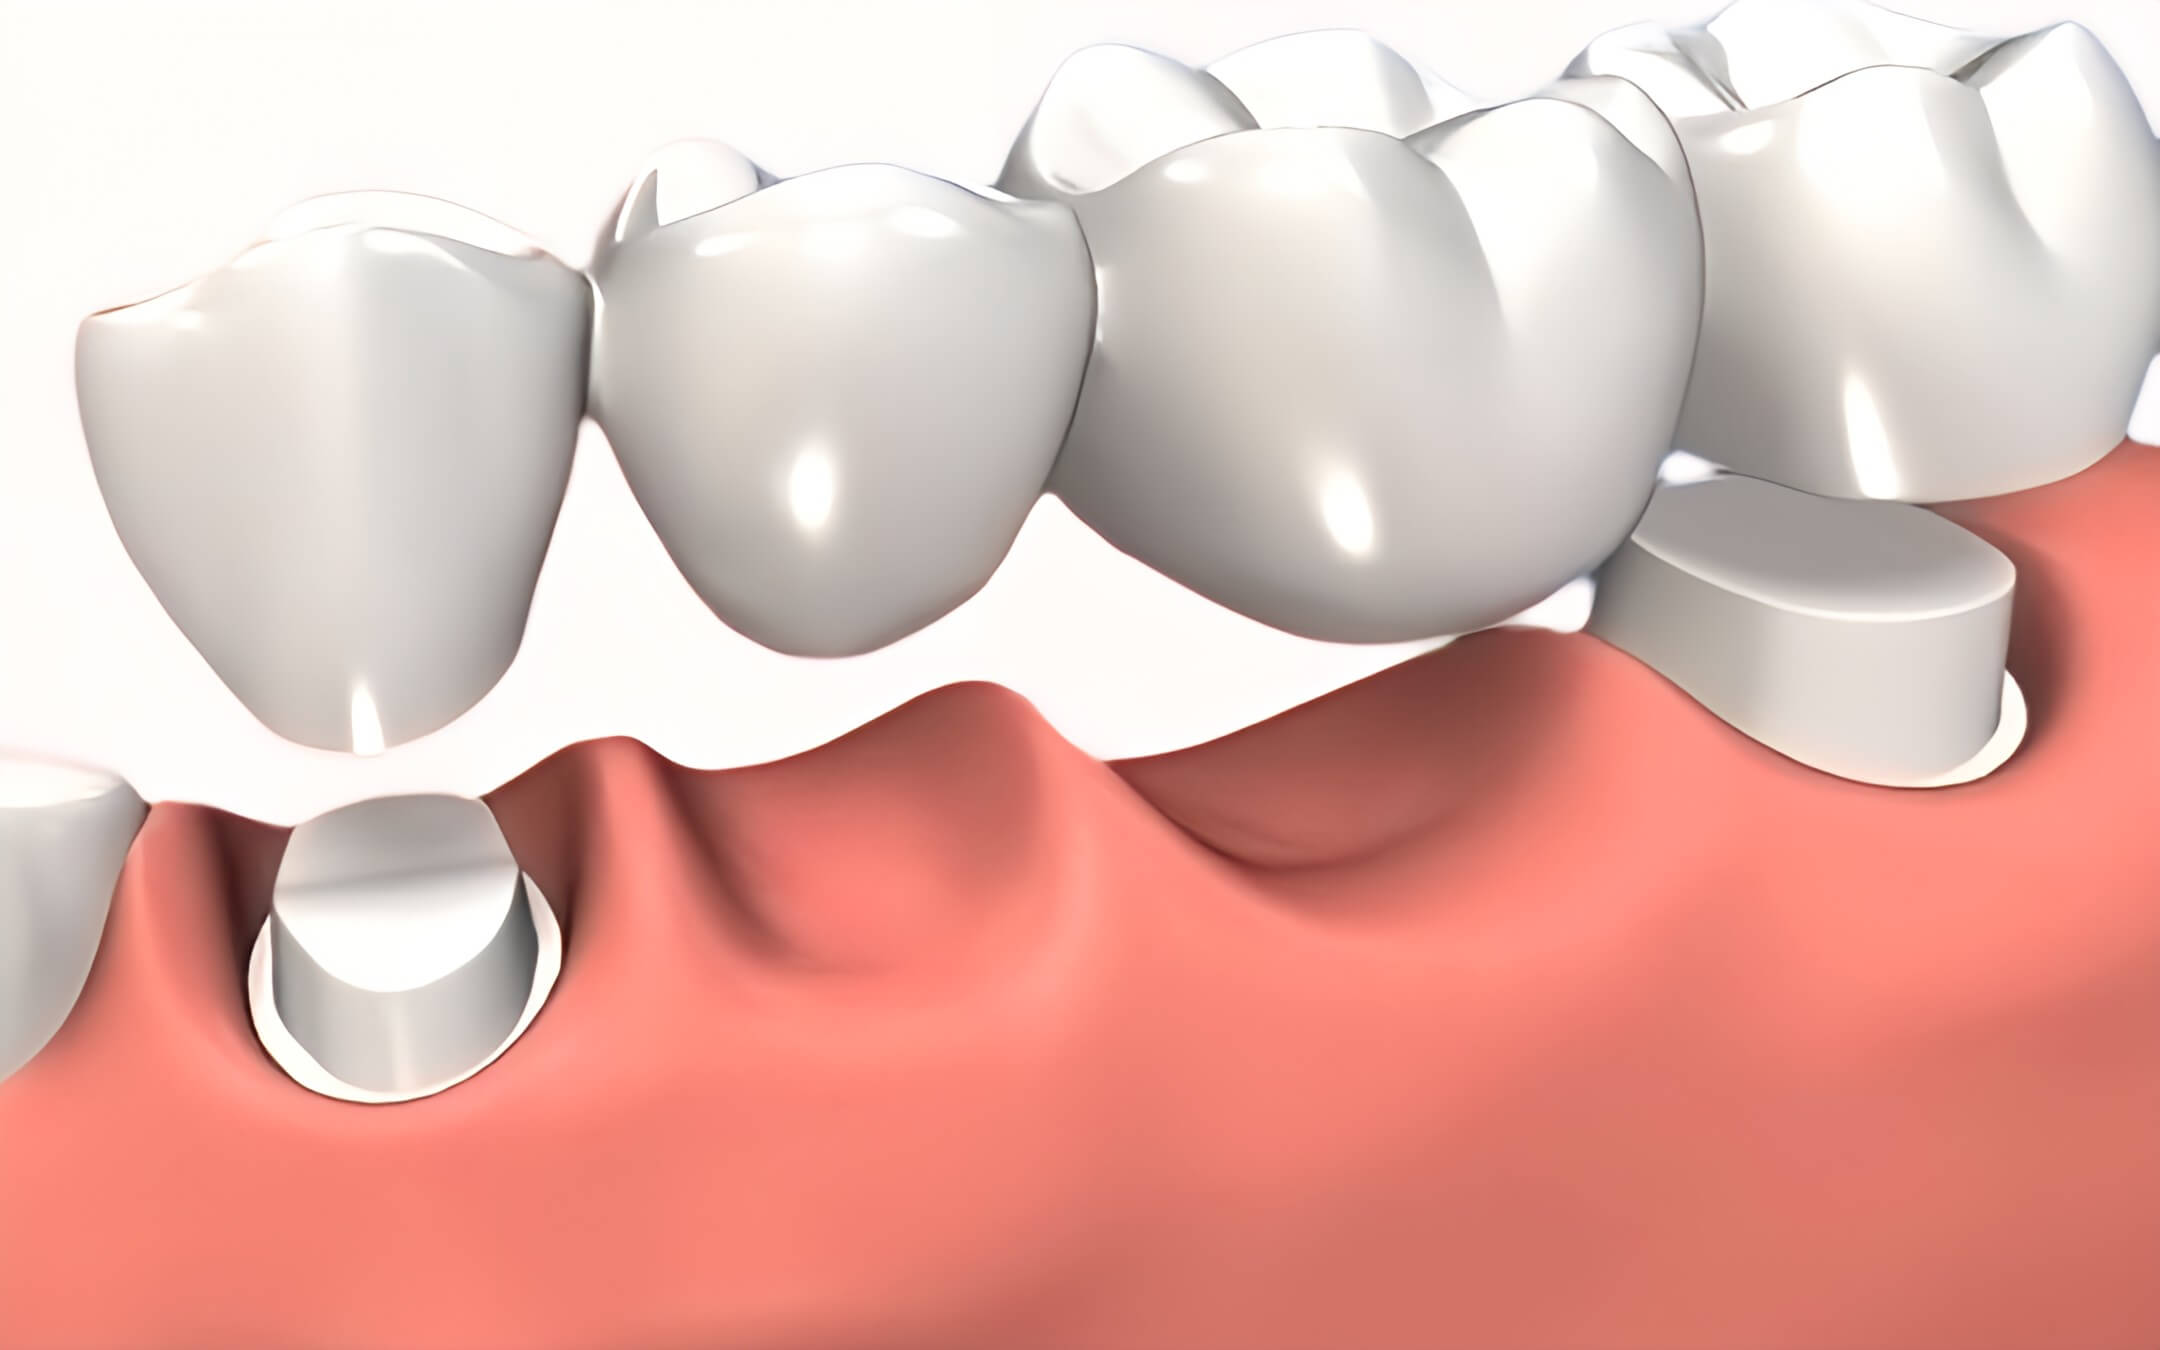

- Puente Dental: Un puente dental es una prótesis que se utiliza para reemplazar uno o varios dientes faltantes. Se sostiene en su lugar utilizando los dientes adyacentes como soporte.

- Implante Dental: Un implante dental es una raíz artificial de titanio que se coloca en el hueso de la mandíbula y se utiliza como base para montar una corona dental.